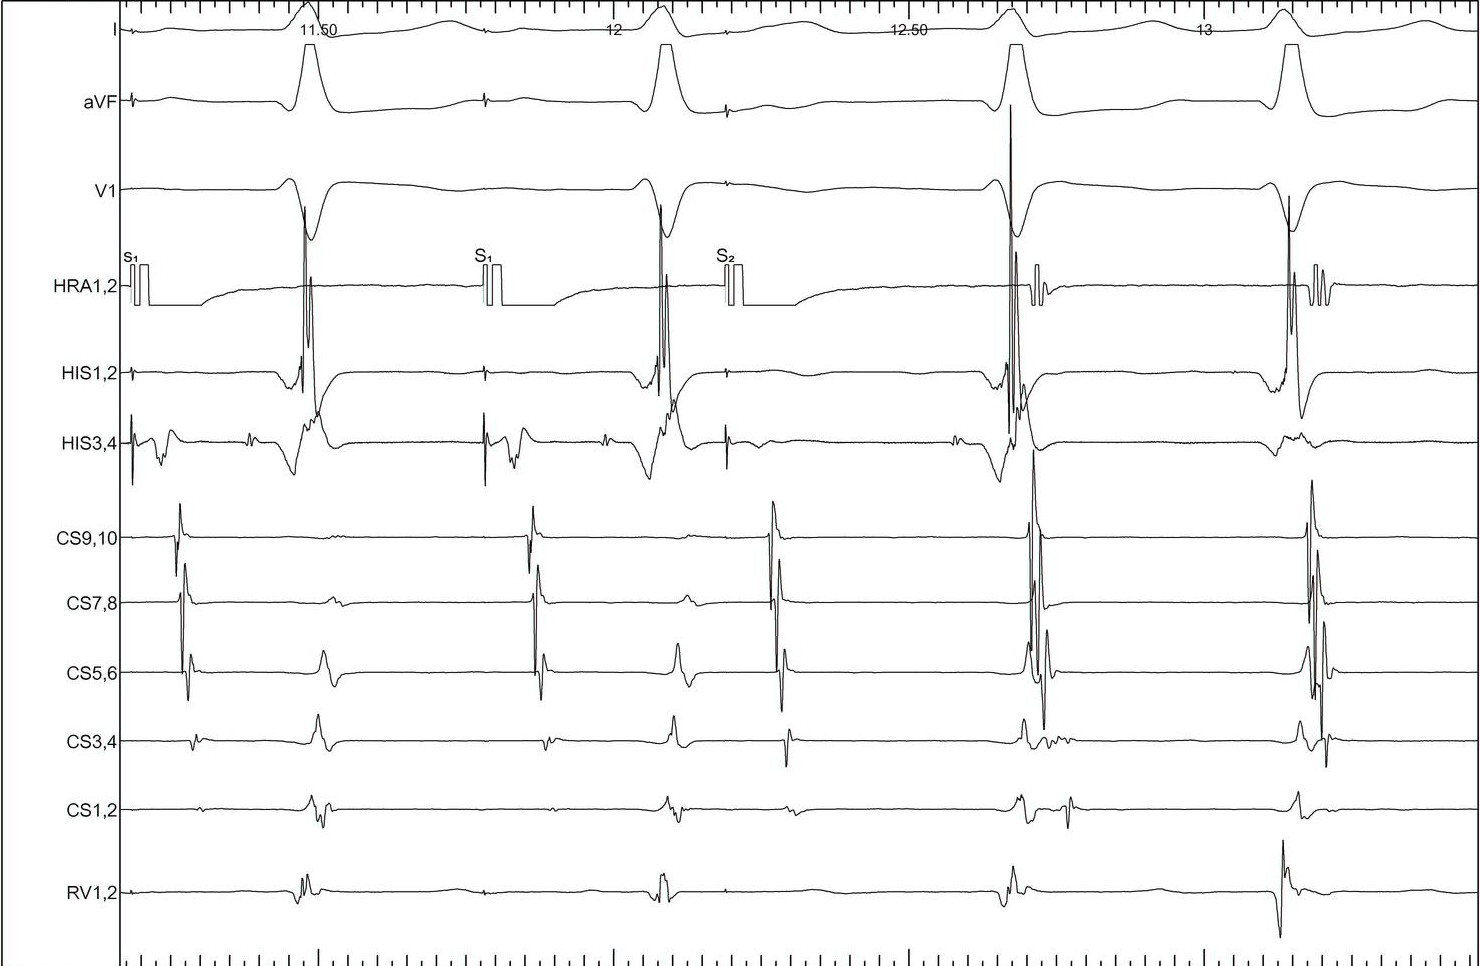

AH jump - 600/430

pre_RA600430.jpg

AH jump - 600/420

pre_RA600420.jpg

AH jump - 600/410

pre_RA600410.jpg